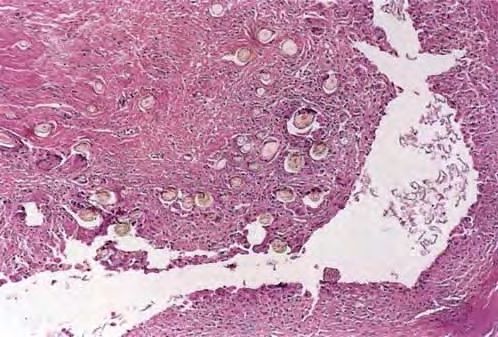

Vellus hair cysts = كيسات الشعر الزغبي